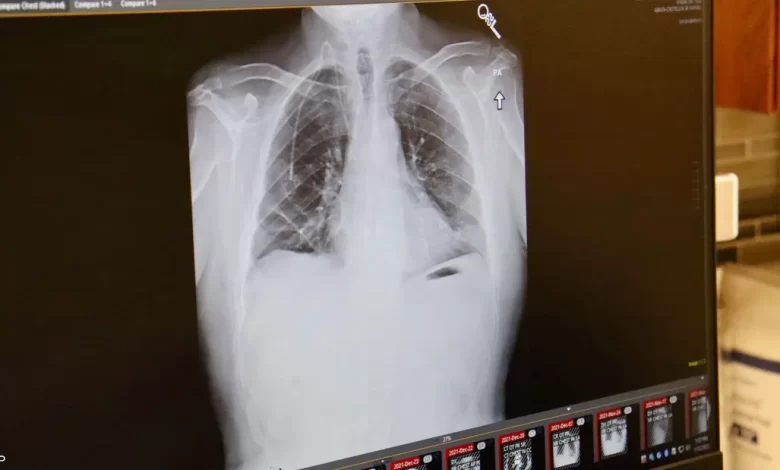

ويعتبر د. شاهين أن سرطان الثدي الأول بالنسبة للنساء في لبنان. أما عند الرجال، فسرطان البروستاتا عند الكبار في السن، وسرطان الرئة والمثانة عند الأصغر سنًا، لا سيما المدخنين، وكذلك سرطان المصران عند الجنسين. ولكن تبقى هذه حالات عادية غير استثنائية يمكن رصدها في معظم البلدان. واليوم، بدأت تظهر أدوية مثل HER2 Positive الذي يشكل نقلة نوعية في علاج سرطان الثدي وهو الأكثر تفشيًا بين النساء، والذي يشكل نسبة 30 إلى 35 % من مجمل أنواع السرطانات في لبنان حسب د. شاهين. وقد يساعد هذا الدواء في زيادة نسبة الشفاء والتقليل من نسبة الوفيات وتحسين وضع المرضى.